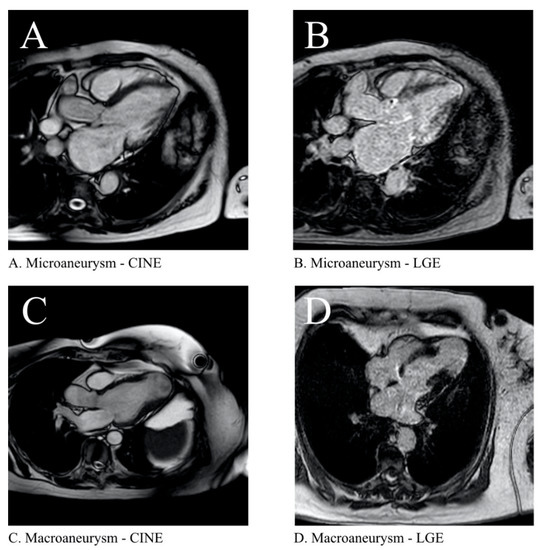

- Duran-Crane, A.; Rojas, C.A.; Cooper, L.T.; Medina, H.M. Cardiac magnetic resonance imaging in Chagas’ disease: A parallel with electrophysiologic studies. Int. J. Cardiovasc. Imaging 2020, 36, 2209–2219. [Google Scholar] [CrossRef]